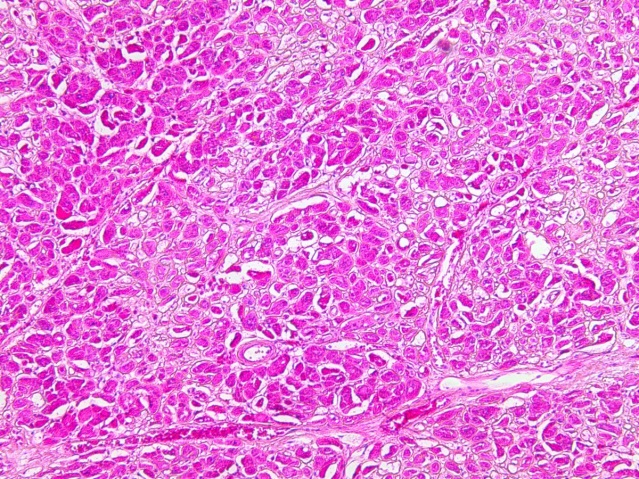

При исследовании ткани легких в стенке сосудов видны плотные гомогенные массы, дающие положительную реакцию на амилоид. При исследовании органов в поляризационном микроскопе обнаружено зеленоватое свечение амилоида. В костном мозге скопление клеток, дающих положительную реакцию с моноклональными антителами к CD38 (рис. 5, 6).

Рис. 5. Пролиферация клеток костного мозга. Окраска гематоксилин-эозин, ×200

Патологоанатомический диагноз: Первичный амилоидоз c поражением почек, селезенки, миокарда, легких. Уремия. Водянка серозных полостей.

Таким образом, у больного был амилоидоз с поражением почек, селезенки, сердца и легких. Обнаружение в костном мозге пролиферации лимфоцитов, дающих реакцию с моноклональными антителами к CD38, дает основание предполагать развитие первичного амилоидоза, который связан с гиперпродукцией легких цепей иммуноглобулина с последующим образованием в тканях внутренних органов AL-амилоида.